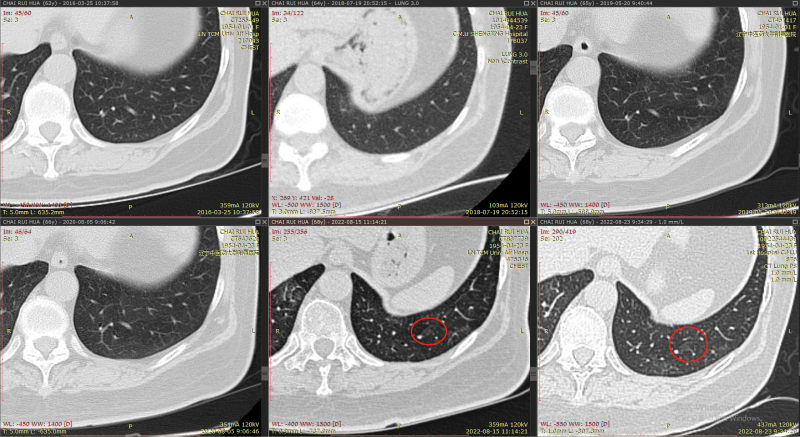

肺部情况:9年前首次发现肺结节,大夫让定期观察,之后每年做一次肺ct,今年6、7月份患者首次接种新冠肺炎疫苗2针剂,7月份患者在中医院体检时接到医院电话,提示肺部结节较以往有增大(以往近五年是0.8,今年是0.9*1.0),肺部有炎症,让进一步确诊。

2022.7.26-8.05日在中医院住院输液头孢8天消炎,8月5日高分辨率CT复查,大夫说通过高分辨CT发现磨玻璃结节上有毛刺,不太好,让到省内权威的中国医大一院复诊,8.23日中国医大一院让在本院做64排薄层ct,大夫说我母亲肺结节为多发,从这么多年看,结节发展较慢,惰性较强,可以先用拜复乐消炎,2个月后复查肺CT和CEA、NSE、肺癌7抗体的血液检查。

结节1:

2013年

2016年-2022年

右肺下叶背段纯磨玻璃结节,最大截面约0.9cm×0.9cm,平均CT值约-431Hu,结节呈类圆形,其中可见小空泡,病灶边界清楚,与9年前CT片比较,病灶密度、大小均无明显变化,考虑为微浸润性腺癌-浸润性腺癌,以微浸润性腺癌可能性大。